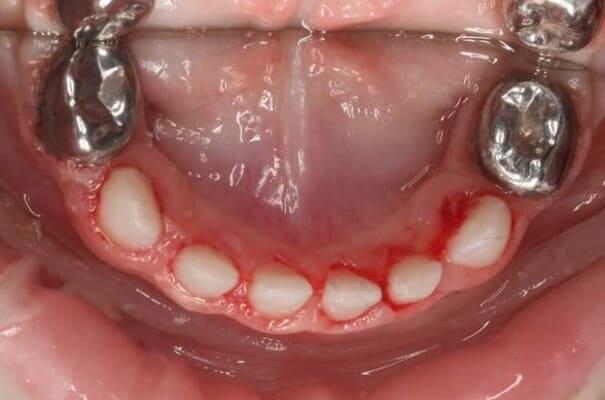

Маленька дівчинка двох років. Лікування проводилось в умовах анестезіологічного забезпечення. Завдяки злагодженій команді анестезіологічної та стоматологічної команди було проведено складне та об’ємне лікування. Було проведено лікування карієсу, герметизація фігур та лікування пульпіту (запалення «нерва») передніх зубчиків з відновленням естетичними коронками. Також бічні зубчики відновлені коронками металевими. Коронки можна комбінувати: на бічні ділянки встановлювати металеві, а на передні зубчики естетичні, щоб забезпечити оптимальну функцію та естетику.